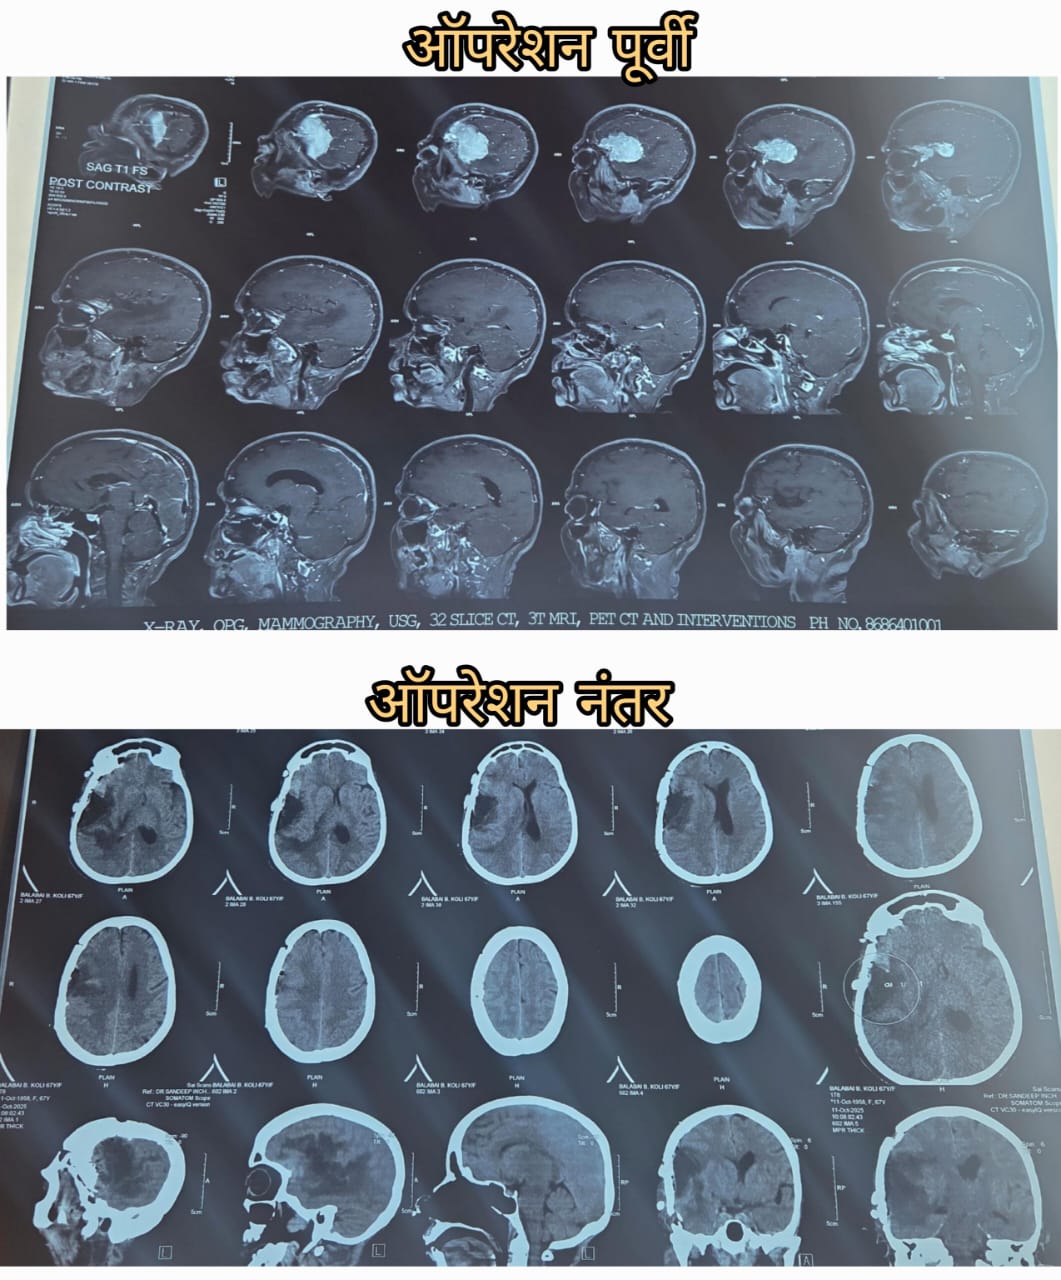

"मेंदूची गाठ " ('Brain Tumour')

क्लिष्ट गाठीवर केलेली मात - ब्रेन ट्युमर वर विजय

डॉ. संदीप इंचनाळकर यांच्या लाईफ लाईन हॉस्पिटलमध्ये एक अद्भुत ऑपरेशन झाले. एका पेशंटला मेंदूची क्लिष्ट गाठ असल्याचे निदान झाले होते. डॉ. इंचनाळकर यांनी त्यांची तपासणी केली आणि ऑपरेशन करण्याचा निर्णय घेतला.

ऑपरेशन यशस्वीरीत्या पूर्ण झाले आणि पेशंटला नवीन जीवन मिळाले. डॉ. इंचनाळकर आणि त्यांच्या टीमने पेशंटला दिलेल्या उपचारामुळे त्यांना पुन्हा एकदा सामान्य जीवन जगता येऊ लागले आहे.

पेशंटला मेंदूची गाठ असल्याचे कळले तेव्हा ते खूप घाबरले होते. पण डॉ. संदीप इंचनाळकर यांच्या सल्ल्यामुळे त्यांनी ऑपरेशन करण्याचा निर्णय घेतला. ऑपरेशन केल्यानंतर पेशंटला खूप आराम वाटला आणि त्यांना पुन्हा एकदा सामान्य जीवन जगता येऊ लागले आहे.